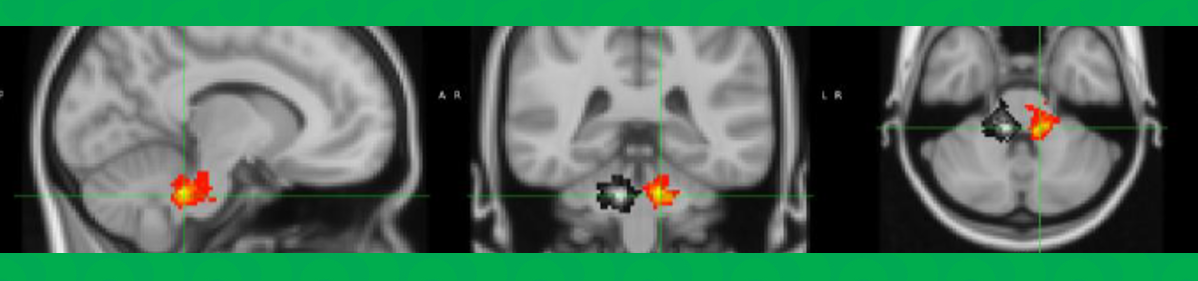

Results

Picture1

Figure 1. PRE > MID. Paired grey matter (GM) CVR difference map expressed in t-values (paired t-test; n=16; p<0.05). Significant decreases in CVR are shown in the left putamen and bilaterally in the cingulate and paracingulate gyrus. Images are in MNI space.

Figure 2. Average (A) PRE (n=18), (B) MID (n=18), and (C) POST (n=16) GM CBF expressed in mL/100g/min. Images are in MNI space.

Discussion

• Our results demonstrate that nonconcussive head impacts may lead to decreased CVR and possibly increased CBF, suggesting vascular dysfunction2 and compensatory hyperemia7

• These metrics show promise as early biomarkers of trauma-related brain changes in contact sports. Longitudinal studies should assess long-term consequences of observed CBF/CVR change